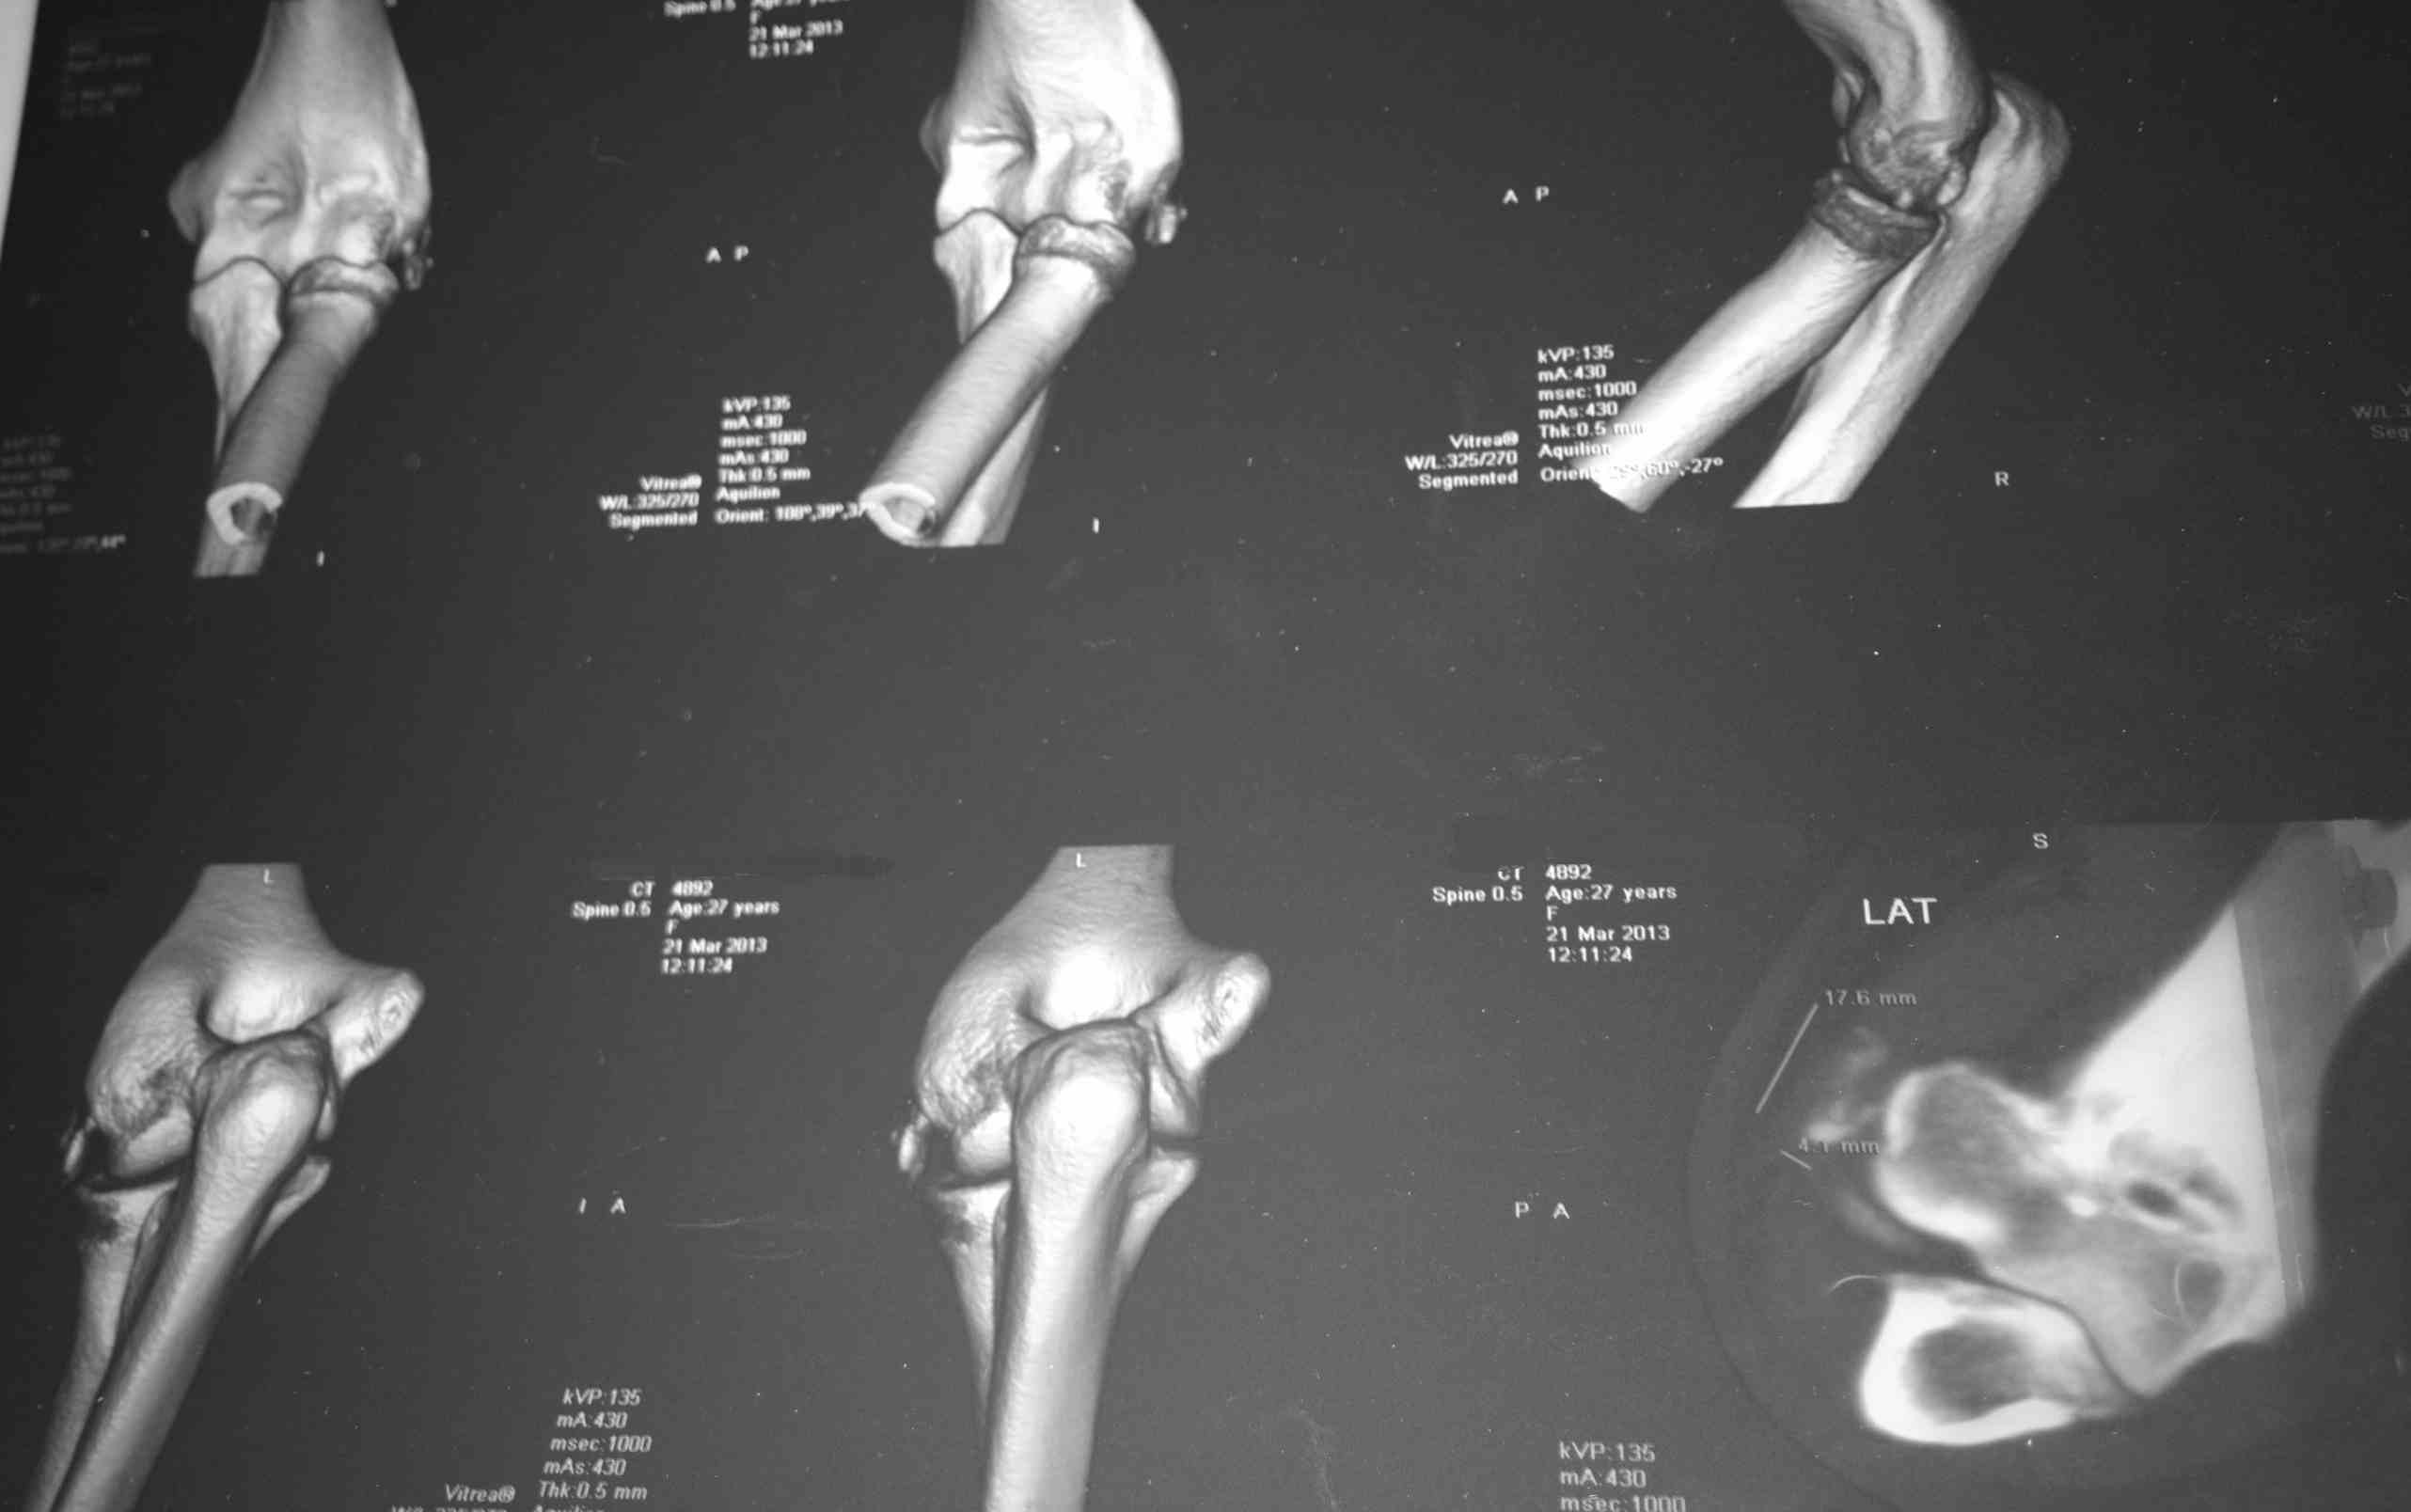

коллеги, помогите опредилиться с диагнозом

На заочную консультацию обратилась девушка, текст переписки и снимки

прилагаю: "Мне 27 лет. 15 марта заболела рука (левая; и я НЕ левша) в

области локтевого сустава; не падала, тяжести не таскала, может недели

за две до этого немного стукнулась локтем, но я полагаю, что если бы это

было причиной, то боль появилась бы сразу, а не через 2 недели. Для

общей картины еще-в 1995 году был перелом локтевой кости(трещина) и

лучевой (закрытый со смещением) в области

лучезапястного сустава). Симптомы: боль в локтевом суставе при

сгибании\разгибании. Больно,но терпеть можно. 16 марта: рука ограниченно

движется-процентов на 40 из всего во

возможного, боль усилилась, Сделали рентген( в больнице "X")-поставили

диагноз- латеральный эпикондилит. С 17 марта боль стала адской, рука

характерна такая клиника и картинка? Для латерального эпикондилита такая

"отшнуровка" нехарактерна. В каком направлении размышлять, какое

дообследование

назначить?